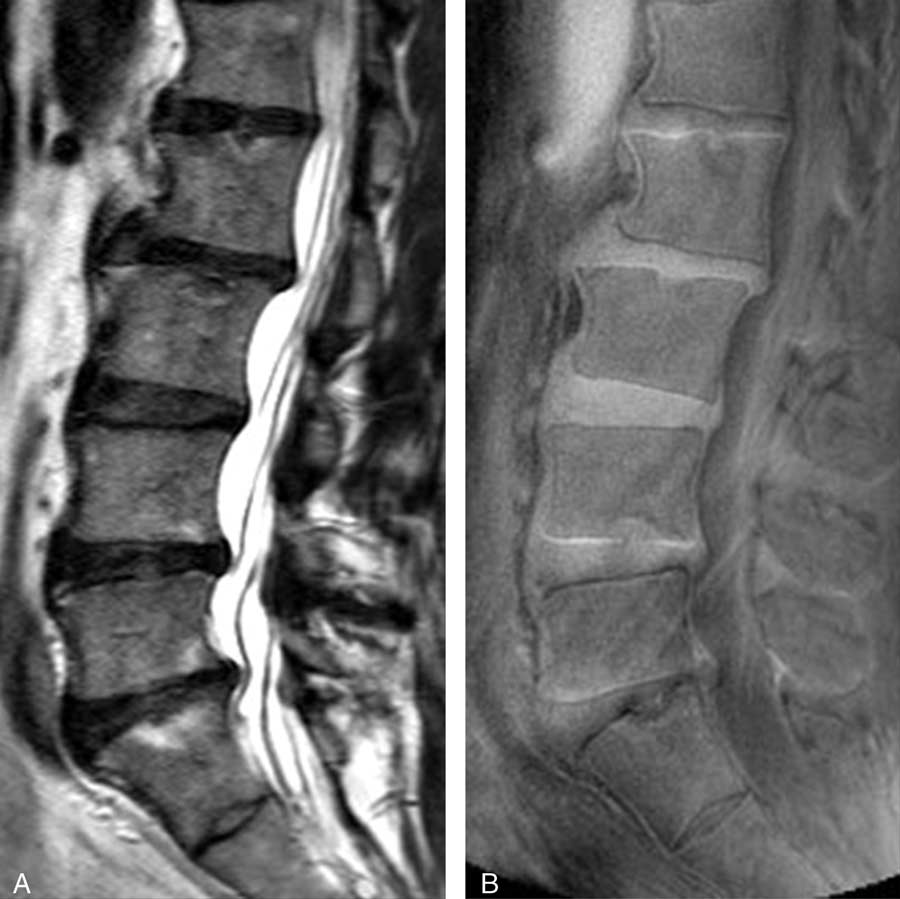

近年世界各地的研究人員都致力研發各種新款的磁力共振技術,希望能為腰椎退化及腰背痛的診斷邁進一步。當中一項嶄新的影像技術為超短時間回波磁力共振(UTE MRI),它能分析人體中含有短回波的軟組織,而這亦是傳統MRI所不能檢測及分析到的。港大的研究團隊利用了UTE MRI技術,首次於人體發現一種名為UTE 椎間盤病徵(UTE Disc Sign / UDS)的嶄新影像指標,在腰椎退化及腰背痛的臨床診斷上帶來重大的啟示。UTE MRI可在現有的MRI儀器上進行,只需約15-20分鐘便能完成掃瞄,與傳統的MRI所需時間相約。

這次研究共有108名華南地區人士(平均年齡52歲,男女各半)參與。傳統的T2W MRI用作評估椎間盤退化和其他影像病徵,T1-rho MRI用作量度構成椎間盤的主要成份 “蛋白聚醣”水平。UDS 病徵被定義為在UTE MRI上檢測到的超高或超低光束帶。參與者的基本資料、病歷、腰背痛情況及活動能力指標(ODI Oswestry Disability Index)亦於研究時採納為臨床指標之一。

研究結果發現39.8%的參與者有UDS病徵,而其中61.4%的UDS是發生於下腰部位置。有UDS病徵比沒有UDS病徵的參與者有更多機會患有椎間盤退化、椎間盤突出、脊椎移位及椎體變異(Modic Change)。有UDS病徵的椎間盤的蛋白聚醣含量比沒有UDS的椎間盤低。而逾六成UDS病徵是無法在傳統的T2W MRI上檢測到。有UDS病徵的參與者比沒有的參與者有更嚴重的腰背痛,而同時其活動能力亦較差,而傳統的T2W MRI並無法找出此關連。研究更指出約四成患者於多節腰椎皆出現UDS病徵,其患上嚴重腰背痛的機率比單節腰椎出現UDS的患者更高。